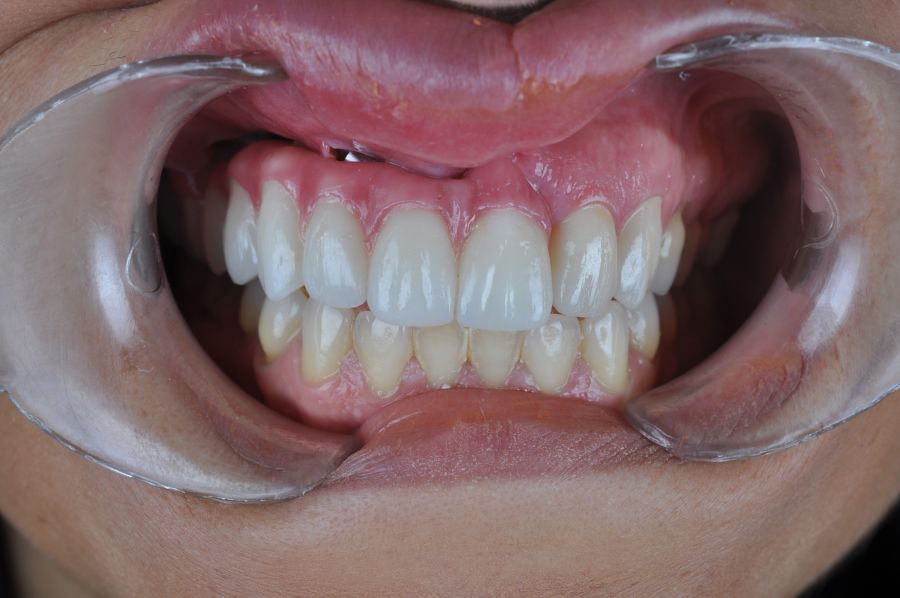

El día de la colocación de las estructuras, se arenó el interior de las coronas dentosoportadas con óxido de aluminio de 50 m y fueron cementadas con cemento de resina Multilink Ò. El puente implantosoportado se atornilló al torque indicado (20Nw) (Figuras 14, 15, 16 y 17).

Las impresiones analógicas y el posterior flujo digital permitieron una correcta planificación protésica. Las estructuras definitivas, confeccionadas en óxido de zirconio monolítico sobre interfases metálicas de titanio, mostraron una adecuada adaptación pasiva tanto clínica como radiográficamente. La prueba estética permitió ajustes oclusales y funcionales mínimos, optimizando el resultado final.

En enero de 2021, el puente implantosoportado fue atornillado con un torque controlado (20 Nw), y las coronas dentosoportadas cementadas con éxito. La paciente refirió una notable mejoría en la función masticatoria, fonación y estética facial, manifestando un alto grado de satisfacción.

En el seguimiento a 4 años tras la colocación de la prótesis definitiva, no se observaron complicaciones mecánicas ni biológicas. La paciente continúa libre de enfermedad y con una correcta adaptación al tratamiento rehabilitador implantosoportado (Figura 18).